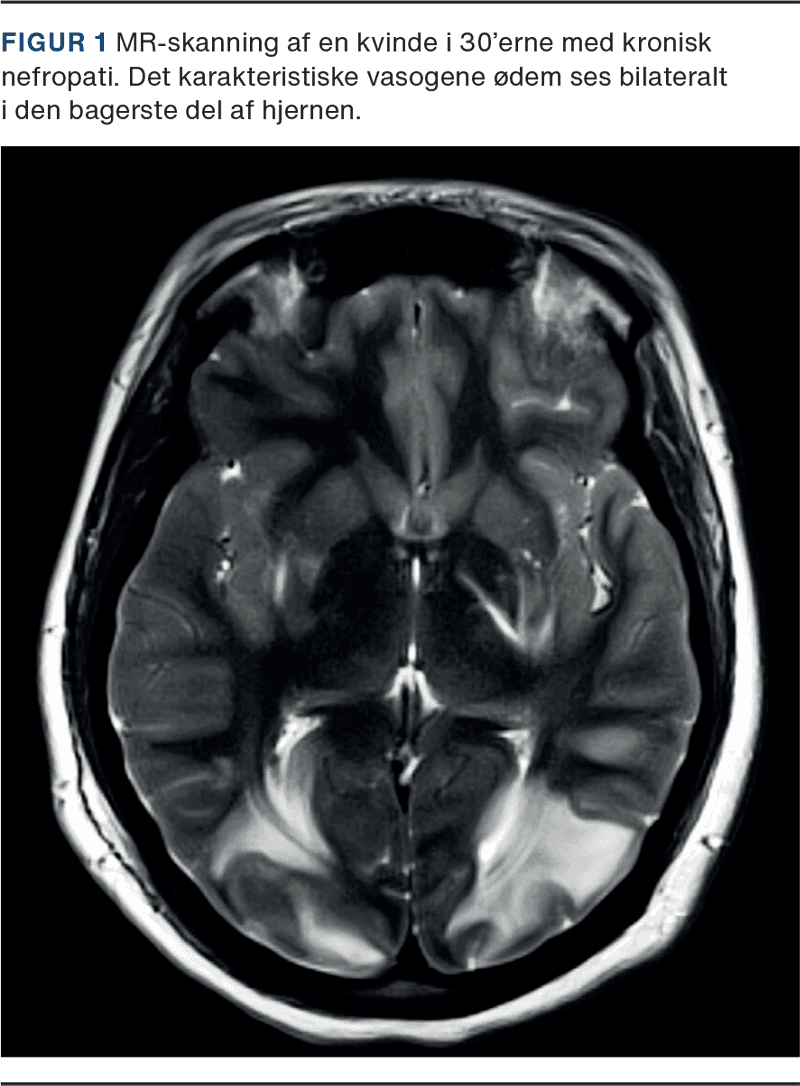

Posteriort reversibelt encefalopatisyndrom (PRES) viser sig klinisk i form af hovedpine, encefalopati, epileptiske anfald og synsforstyrrelser. Typiske radiologiske fund er vasogent ødem primært i hjernens parietal- og occipitallapper.

Posteriort reversibelt encefalopatisyndrom (PRES) er et neurologisk syndrom, som omfatter hovedpine, encefalopati, epileptiske anfald og synsforstyrrelser. De typiske billeddiagnostiske fund er vasogent ødem overvejende i hjernens occipital- og parietallapper [1]. PRES blev først beskrevet i 1996 [1]. Dengang var navnet reversibelt posteriort leukoencefalopatisyndrom (RPLS), men navnet PRES er nu det mest anvendte. Oprindeligt betragtede man PRES som fuldt reversibelt [1], men det har siden vist sig ikke altid at være tilfældet [2].

PRES-diagnosen bekræftes ved hjælp af billeddiagnostik af hjernen. MR-skanning foretrækkes frem for CT grundet dens overlegne opløsning. De typiske billeddiagnostiske karakteristika for PRES inkluderer vasogent ødem i den hvide substans og ofte i den overliggende cortex. PRES erkendes bedst på MR-skanning med fluid-attenuation inversion recovery-sekvenser (FLAIR) [19].

Parietallapperne og occipitallapperne er næsten konsekvent involveret, og man ser typisk, at fundene er symmetriske og bilaterale. Der kan ses involvering af frontallapperne i nogen grad, specielt nær de superiore frontale sulci. Selv om vasogent ødem kan påvirke den grå substans, observeres det oftere og tydeligere i den subkortikale hvide substans [19].

Intrakranielle blødninger findes i den akutte fase i 10-25% af tilfældene [21]. Men op til 65% af patienterne, der får udført opfølgende MR-skanning, har mikroblødninger [21] (Figur 1).